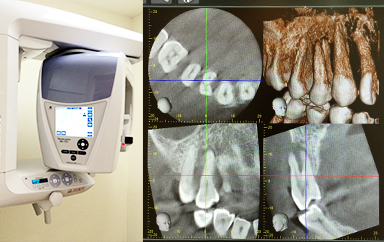

口腔内を3次元的にとらえることができ、詳細な精査、診断が可能です。

最新のデジタルレントゲンを導入しています。フイルムによるレントゲン撮影に比べて、放射線の量を大幅に抑えています。